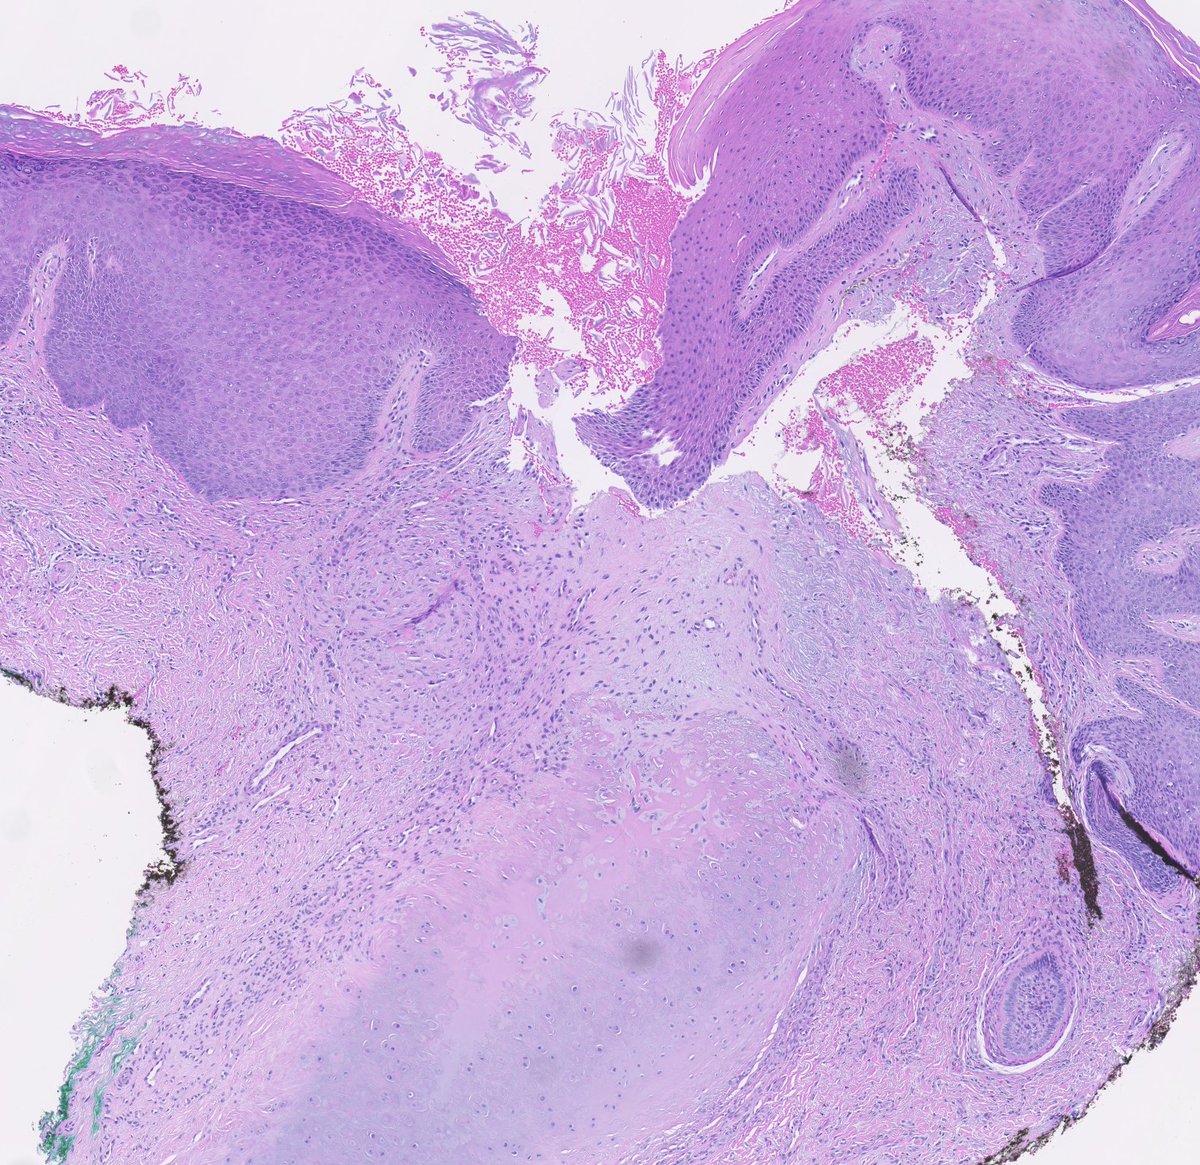

#ISDP #Olympics Spot diagnosis Case 4 - Jose Candido EXTRAMAMMARY PAGET DISEASE Intraepithelial proliferation of cells with vesicular nuclei and basophilic/amphophilic cytoplasm. Cells distributed in a solitary fashion or in nest/gland-like structures #derm #path #med

EXTRAMAMMARY PAGET DISEASE

Intraepithelial proliferation of cells with vesicular nuclei and basophilic/amphophilic cytoplasm.

Cells distributed in a solitary fashion or in nest/gland-like structures